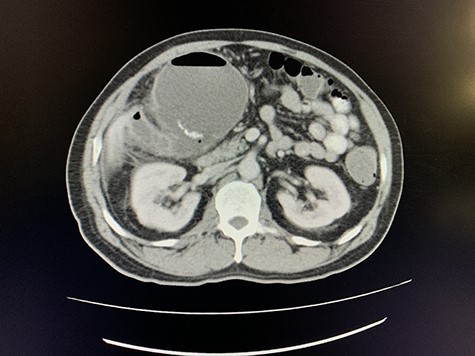

A computed tomography (CT) scan of the abdomen revealed an enlarged, thickened gallbladder with multiple stones, communicating with an intrahepatic collection in segment 4 measuring 116 × 80 mm, with an associated air fluid level and air locules (Fig. 1). There was an apparent fistulous tract to the hepatic flexure of the colon, another large collection in segment 6 (97 × 96 mm) as well as other smaller collections (Figs 2 and 3).

Coronal view of oral and intravenous contrasted CT scan of the abdomen demonstrating features of cholecystitis with fistulous communication with the hepatic flexure of the colon with associated pneumobilia.